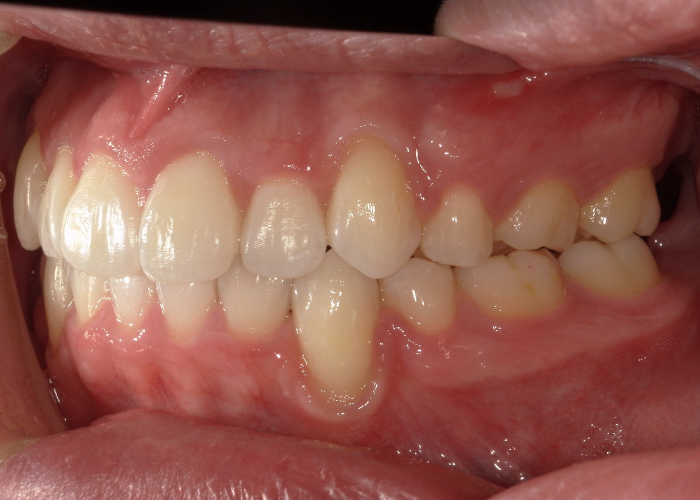

歯のがたつきと出っ歯が気になる